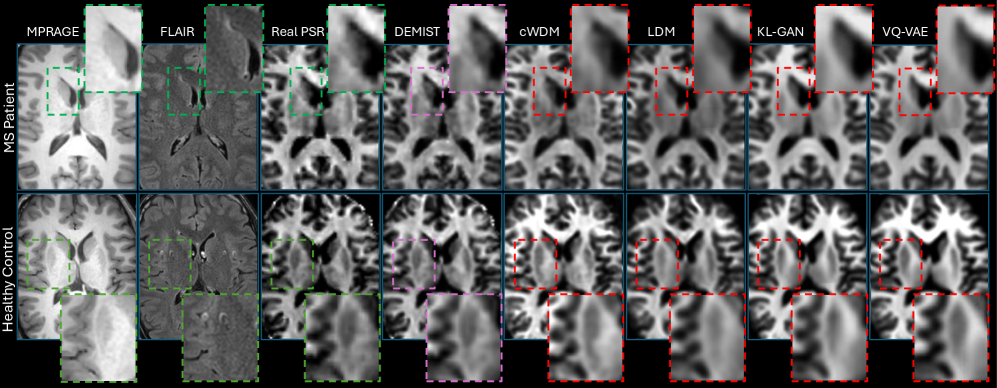

Fig. 4: Qualitative results. Each row shows conditions (MPRAGE, FLAIR), ground truth PSR, and synthesized outputs from our method and the baseline methods. Zoom panels highlight our method produces sharper boundaries for the lesion (in top row, an MS patient), and provides more accurate anatomy (highlighted in the putamen shape in the bottom row, a healthy control).

Qualitative Analysis. Figure 4 shows representative results for both MS patients and healthy controls. Our method produces sharper lesion boundaries and better preserves cortical gray-white matter transitions. The GAN-based and VQ-VAE approaches tend to blur fine anatomical details, while the standard LDM and cWDM methods provide fine details but underestimate PSR contrast.